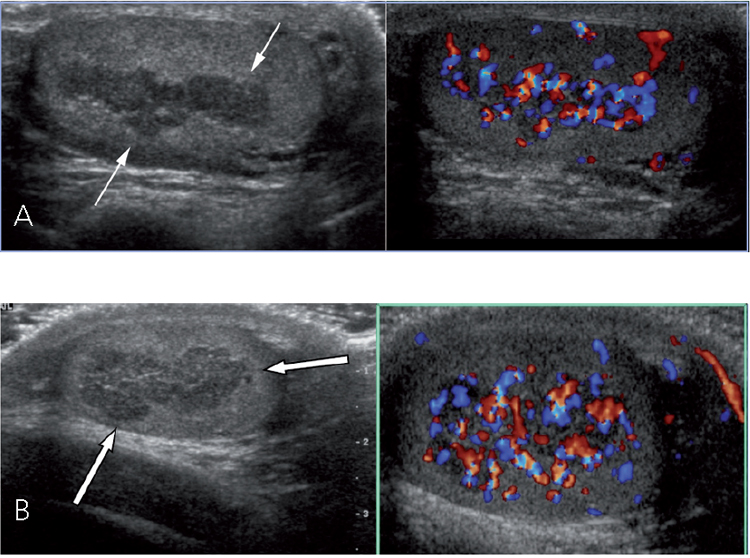

A los 12 años una ecotomografía testicular, realizada en otro centro, demuestra testes de 4,9 cc, y no describen restos adrenales. A los 14 años, se solicita nueva ecografía testicular: Testículo derecho (TD) 6,3 cc; Testículo izquierdo (TI): 6,3 cc. En forma bilateral, adyacente a la región del mediastino testicular, se observan áreas hipoecogénicas, de contornos irregulares, lobuladas en el lado izquierdo, donde adquiere aspecto multinodular; miden 1,6 x 0,6 cm a derecha y 2,0 x 0,5 cm a izquierda. El estudio Doppler color demostró escaso flujo vascular en el espesor de estas áreas. No hay calcificaciones. El flujo vascular del resto del parénquima testicular es cualitativamente normal en ambos lados. En la cabeza del epidídimo derecho se observa un pequeño quiste ovalado de 0,4 cm. No hay signos de hidrocele ni varicocele. Las imágenes ecográficas corresponden a restos suprarrenales y a un quiste de epidídimo.

El control de laboratorio demostró: 17OH-Progesterona 290 ng/mL, androstenediona 16 ng/mL (VN 0,3 a 3,1), lo que sugieren un inadecuado cumplimiento del tratamiento. Para descartar la presencia de posibles tumores supra-rrenales se realiza TAC suprarrenal que muestra moderado engrosamiento de ambas astas suprarrenales, impregnación homogénea con el contraste endovenoso, sin lesiones nodulares. Se enfatiza al paciente y su familia las reper-cusiones sobre fertilidad por la presencia de restos adrenales y de la necesidad urgente de una adecuada adherencia al tratamiento (Tabla 1). A la edad de 17 años, considerando que su velocidad de crecimiento era 1,5 cm el último año y su EO de 17 años, se inicia prednisona 2,5mg c/12 h que posteriormente se aumenta a 2,5 y 5 mg/d. Una nueva ecotomografía testicular demostró persistencia de los restos adrenales, teste derecho de 6,6 cc e izquierdo de 7 cc (Figura 2), lo que evidencia un crecimiento testicular absolutamente inadecuado considerando que ya tenía 6 años de evolución puberal.

Figura 2. Ecografía con Doppler color. A: Testículo izquierdo. Las flechas blancas indican los Restos testiculares de glándula suprarrenal. B: Testículo derecho. Las flechas blancas indican los Restos testiculares de glándula suprarrenal.

Las ecotomografías Doppler color fueron realizadas por uno de los autores (CG) usando un transductor de alta resolución de 12 mHz. El tamaño testicular se evaluó por imágenes congeladas. El volumen testicular como el tumoral fue calculado usando la fórmula: V = L x W x D x 0,52, donde V es volumen (mL), L es la longitud máxima (cm), W es el ancho máximo (cm), and D es la profundidad máxima (cm).